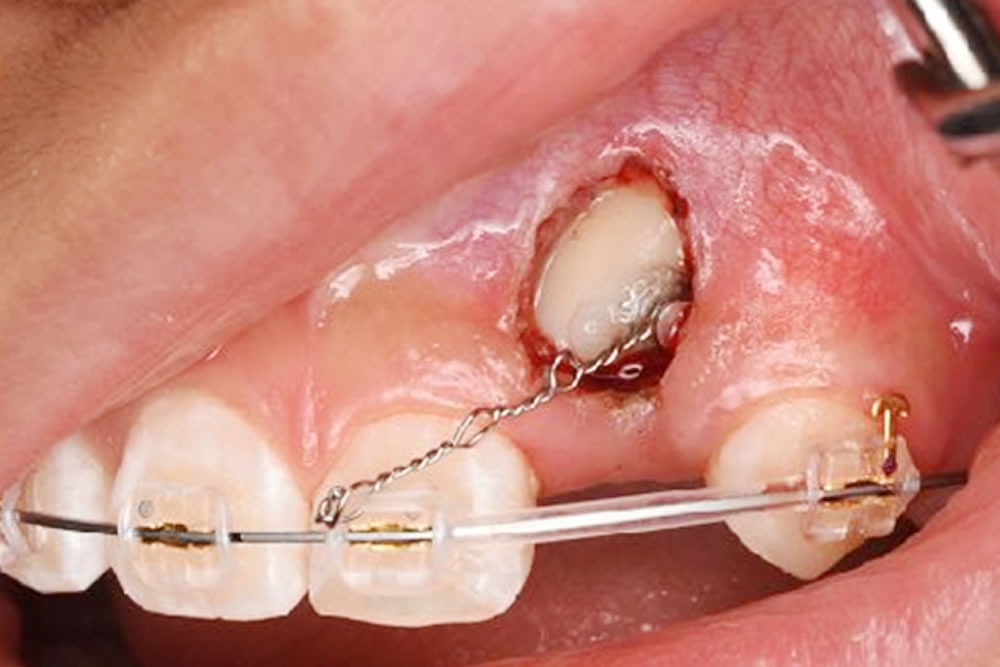

2.開窓牽引

前述した萌出スペースの確保を行い歯が自然と生えてこない場合は、歯に萌出力が残っていないと判断し、開窓牽引により矯正力をかけてあげて、歯が萌出する手助けをしてあげます。

本症例では、残念ながら自然と萌出してくることがなかったため、矯正装置を変更し、マルチブラケット装置によるワイヤー矯正によって開窓牽引を行いました。